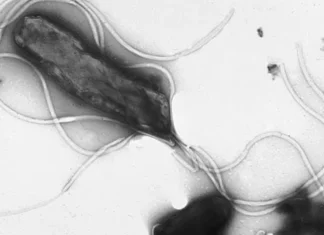

연구 결과 과일 섭취량이 많은 그룹은 적은 그룹보다 위암 발생 위험이 평균 11% 낮은 것으로 관찰됐다. 과일에 풍성한 비타민C, 폴리페놀, 식이섬유 등의 항산화·항염증 성분이 위암 주범 중 하나인 헬리코박터 파일로리균이 만들어내는 발암물질 형성을 억제한다는 게 연구팀 설명이다.

또 이들 성분이 위 점막과 유전자 손상을 막고 위축성 위염의 위암 진행을 막는 데도 큰 역할을 하는 것으로 봤다. 다만 과일은 주스 형태보다는 통째로 먹는 게 더 효과적이었다.

위 점막 세포의 비정상적인 증식과 변형을 유도하고 헬리코박터 파일로리균 감염에 대한 위 점막의 민감도를 증가시켜 암 발병률을 높인다는 것이다. 또 위 내 염분 농도가 높아지면 점막 자극을 통해 장상피화생(위암 전 단계로 위 점막이 소장·대장 점막과 유사하게 바뀌는 증상)을 유도할 수도 있다.